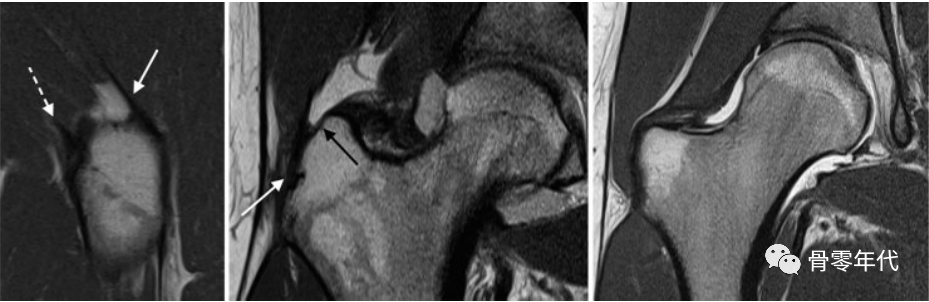

(a)冠状面T2加权像上的外侧臀中肌部分厚度撕裂(箭头),以及(b,c)外展肌腱的全层撕裂(b和c中的箭头指向臀中肌外侧),臀中肌明显回缩,如冠状面T2加权像(b)和轴向质子密度加权脂肪饱和图像(c)所示。

71岁女性臀小肌腱部分厚度撕裂(a和b中的箭头):(a)脂肪饱和冠状质子密度加权图像和(b)轴位T2加权脂肪饱和图像,伴有明显增厚和相关的小粗隆滑囊炎(b,虚线箭头)。(c)臀小肌腱在矢状位T1加权像上信号强度增加(星号)反映潜在的肌腱病变。